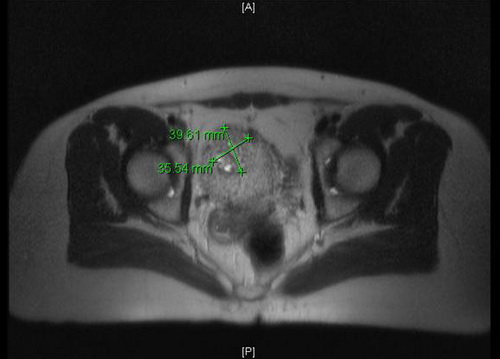

MRT: Vergrößerter anteflektierter Uteus. Im Cavum uteri inhomogen kontrastierte Läsion von 2,9 × 4,4 cm mit teils liquiden Anteilen, vereinbar mit der bekannten Blasenmole. Vermehrte retroperitoneale Lymphknoten nicht suspekt vergrößert.